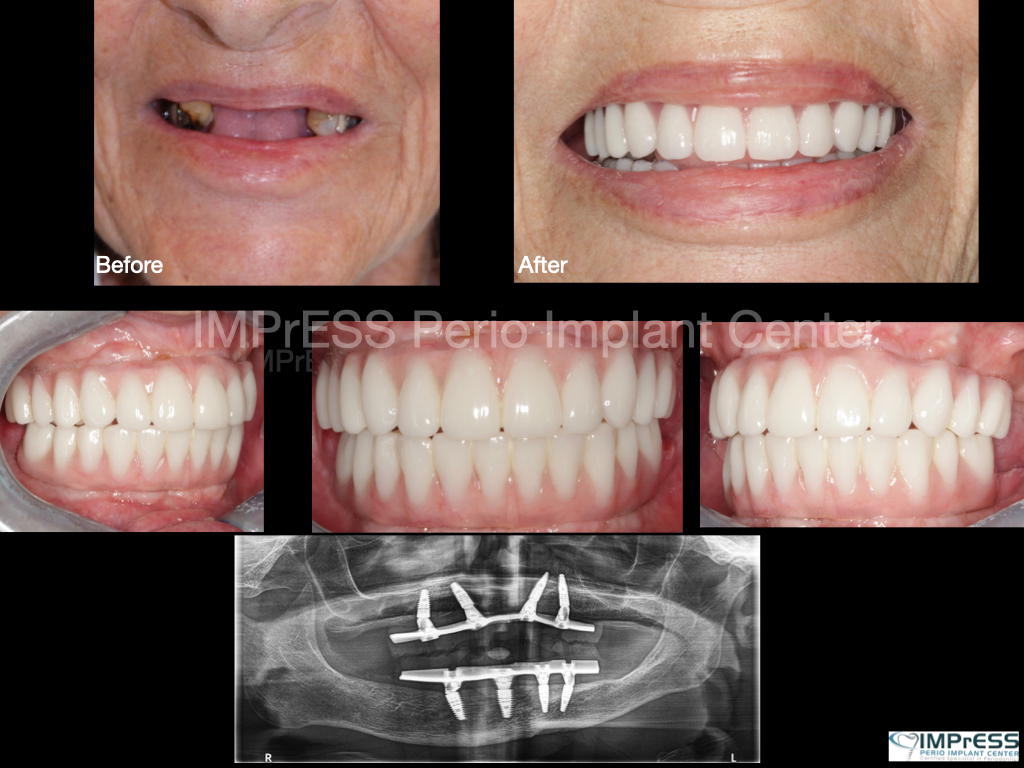

Before & Afters of Dental Implant Patients

Complete Dental Implant Cases Gallery

• When replacing several teeth or all of your teeth, a fixed bridge is anchored to your dental implants. A bridge is a dental restoration that replaces one or more missing teeth by spanning an area that has no teeth. The bridge is held firmly in place by dental implants on each side of the missing tooth or teeth.

Dental implant treatment is sometimes a team effort between your periodontist and a restorative dentist.  Dr. Noroozi  at IMPrESS Perio Implant Center located in Burnaby BC performs the actual implant surgery, initial tooth extractions, and bone and gum grafting if necessary.  The restorative dentist (your dentist) or our specialists (if you do not have a dentist) will fit and make the permanent prosthesis. Your dentist or our specialists will also make any temporary prosthesis needed during the implant process.

General Disclaimer: The results in the photographs are examples only and do not imply any certainty of the result of a procedure, and all outcomes are subject to the circumstances of the individual patient.